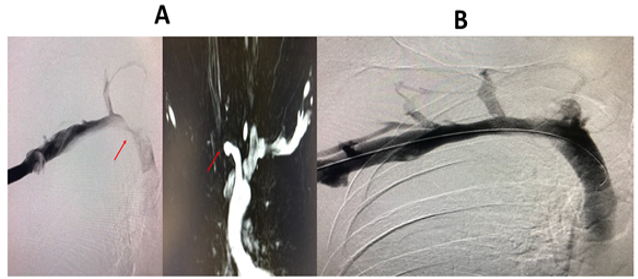

Observations in patients with a previous diagnosis of Neurogenic TOS who had persistent upper extremity neurologic symptoms following first rib resection by the transaxillary and supraclavicular approaches, revealed persistent extrinsic compression of the subclavian innominate junction on dynamic MRA. Disarticulation of the cost-sternal joint and removal of the remaining portion of the first rib, which bore a tubercle similar to that which was seen in patients with Paget Schroetter syndrome, resulted in relief of neurologic symptoms in all patients. In turn, Postoperative MRA and Venogram showed relief of extrinsic compression and decompression of the subclavian innominate junction. (Figures. 5a, 5b) This observation, in addition to the observation that patients with PSS have diffuse neurologic symptoms of the upper extremity prior to clotting of SV, led to the hypothesis that in a subgroup of patients with DNTOS, upper extremity neurologic symptoms may be due to venous compression and the resultant venous ischemia of the nerves in the upper extremity. This hypothesis is supported by the fact that the upper extremity is fed by a single artery and a single vein as an “end organ.” In such a setting, studies have demonstrated that the blood-nerve barrier in the nerve root was more easily broken by venous congestion than by arterial ischemia. Venous congestion may be an essential factor precipitating circulatory disturbance in nerve roots and inducing neurogenic intermittent claudication. This phenomenon is illustrated by the feeling of a leg “falling asleep” or pain and paresthesia which is experienced in the lower extremity after crossing the leg for a prolonged period of time. Of interest, patients with DNTOS liken their symptoms to their arms “falling asleep”.

These observations support the “ischemic” versus the “compressive” pathogenesis of a subgroup of patients with DNTOS. In these patients DNTOS appears to be the manifestation of a congenital malformation of the first rib. The congenital malformation is in the form of a pronounced tubercle, which results in an abnormal costo-sternal joint and the compression of the subclavian vein at its junction with the innominate vein. (Figure. 6) The compression of the subclavian vein in the thoracic outlet results in a spectrum of neurologic symptoms which are the result of venous ischemia of the upper extremity nerves. The ischemic pathogenesis of DNTOS is consistent with the normal neurologic exam and lack of objective evidence for nerve compression in these patients.

Figure 6: Resected specimen of the medial aspect of the first rib at the costo-sternal junction showing the abnormal bony tubercle which results in compression of the subclavian vein (SV) at its junction with the innominate vein (IV).

Magnetic Resonance Angiography clearly demonstrates the extrinsic compression at the subclavian innominate junction and can guide the decision for surgery. The most compelling evidence for ischemic pathogenesis of DNTOS is the relief of symptoms following disarticulation of the costo-sternal joint and removal of the medial aspect of the first rib.